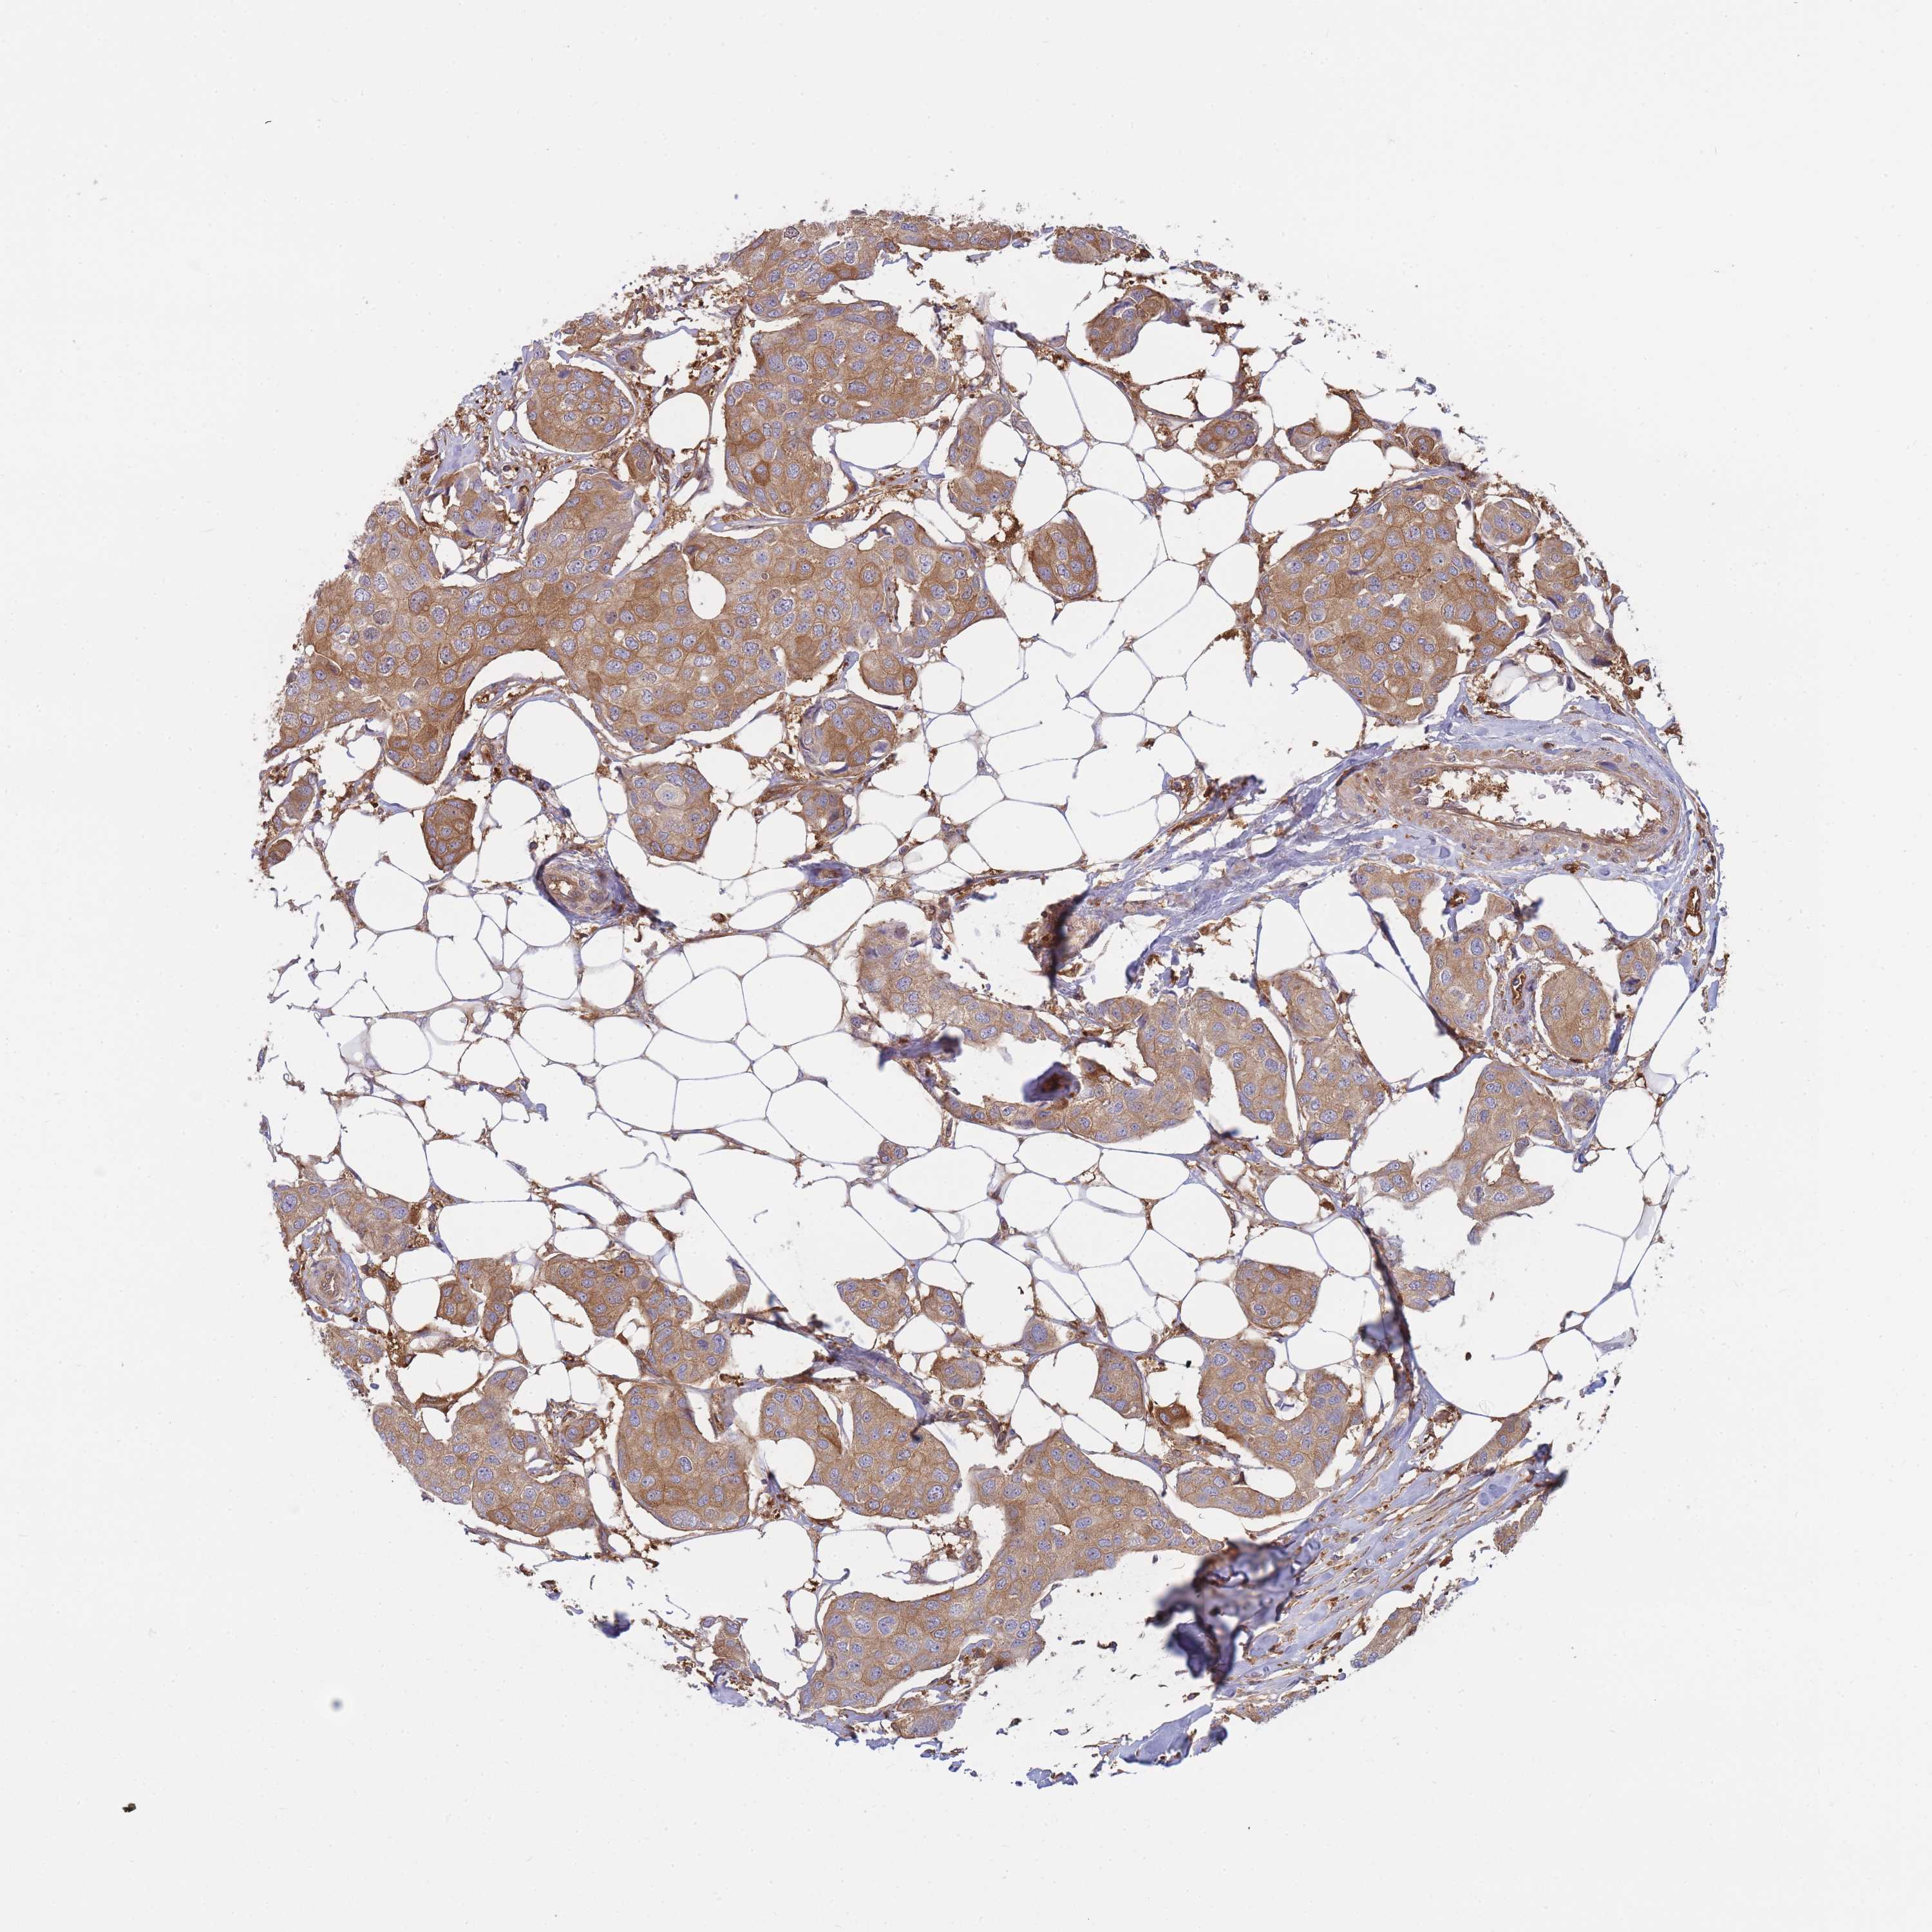

CANCER BREAST CANCER Show tissue menu

Breast cancer

Human cancer

Breast invasive carcinoma